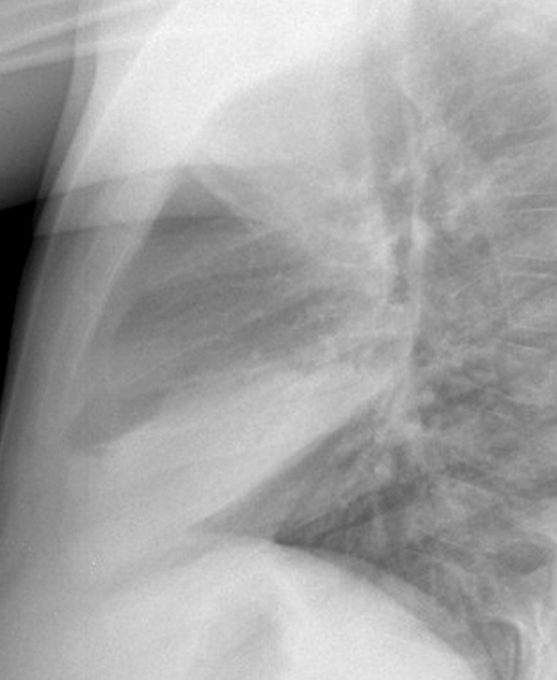

RML collapse